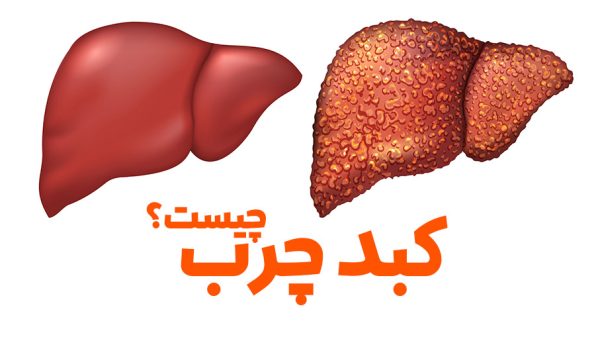

کبد چرب چیست؟

بیماریهای کبد انواع متعددی داشته و هرکدام بهنوعی به این اندام حیاتی آسیب وارد میکنند. کبد چرب یکی از شایعترین بیماری های کبد است که به دلیل تجمع چربی در آن ایجاد میشود. کبد چرب که با نام استئاتوز کبدی نیز شناخته میشود، زمانی اتفاق میفتد که چربی در کبد تجمع پیدا کند.

وجود مقدار کمی چربی در این اندام طبیعی است. اما تجمع بیش از حد آن میتواند به یک مشکل اساسی تبدیل شود. اگر بیش از ۵ تا ۱۰ درصد از وزن کبد شما چربی است احتمالا به این بیماری مبتلا هستید. کبد دومین ارگان بزرگ بدن است. این عضو، به فرآوری مواد غذایی کمک میکند و مواد مضر خون را فیلتر میکند. گاهی این بیماری را بیماری خاموش کبدی مینامند، به این دلیل که میتواند بدون ایجاد علائم رخ دهد.